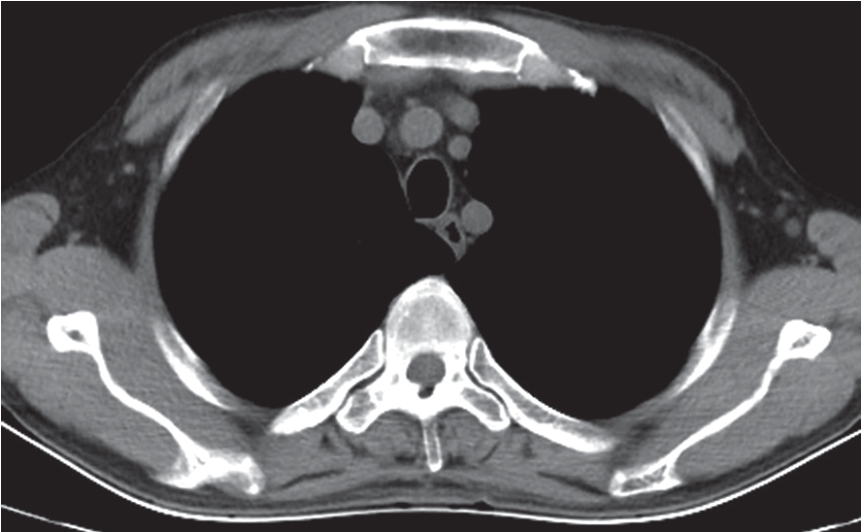

(3)创伤性椎间盘脱出:显示椎间盘局限性突入椎管使硬膜囊变形、脊髓移位(图7-2-15)。

图7-2-15 CT示爆裂性骨折